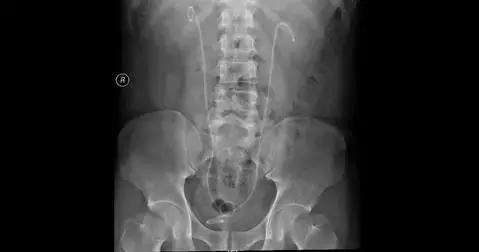

术后KUB

手术过程顺利,左肾输尿管和右肾结石都被彻底清除,小陈前后住院十天也返家休养了。一个月后拔出双“J”管后完全康复。